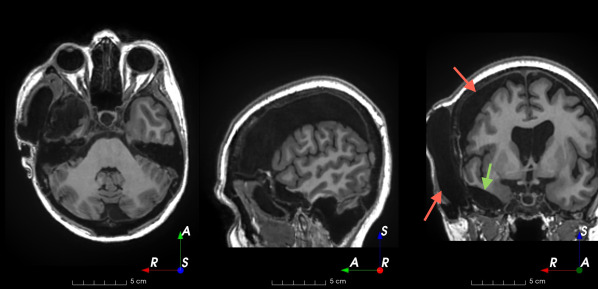

Refer to caption

(a)

(b)

(c)

(d)

(e)

(f)

(g)

(h)

Figure 6: Examples of challenging images for cavity segmentation. (a) Small frontal lesionectomy surrounded by hypointense white matter (b) Brain shift after contralateral temporal lobectomy (not shown) (c) Small frontal lesionectomy near the Sylvian fissure (d) Lack of boundaries between oedema and resection cavity (e) Possible blood clot within the cavity (f) Brain shift, oedema and resection cavity (g) Arachnoid cyst and resection cavity (h) Cerebellar degeneration. Green annotations represent areas that correspond to resection cavities; red annotations represent areas that do not.